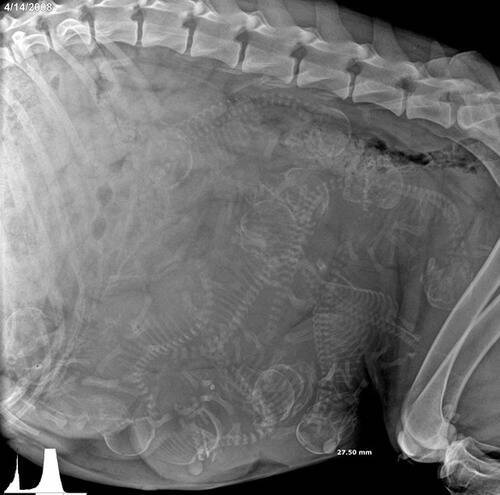

妊娠した犬のレントゲン写真 めちゃくちゃすごかった

これは妊娠中の犬のレントゲン写真 人間とは明らかに違う 16年11月4日 エキサイトニュース